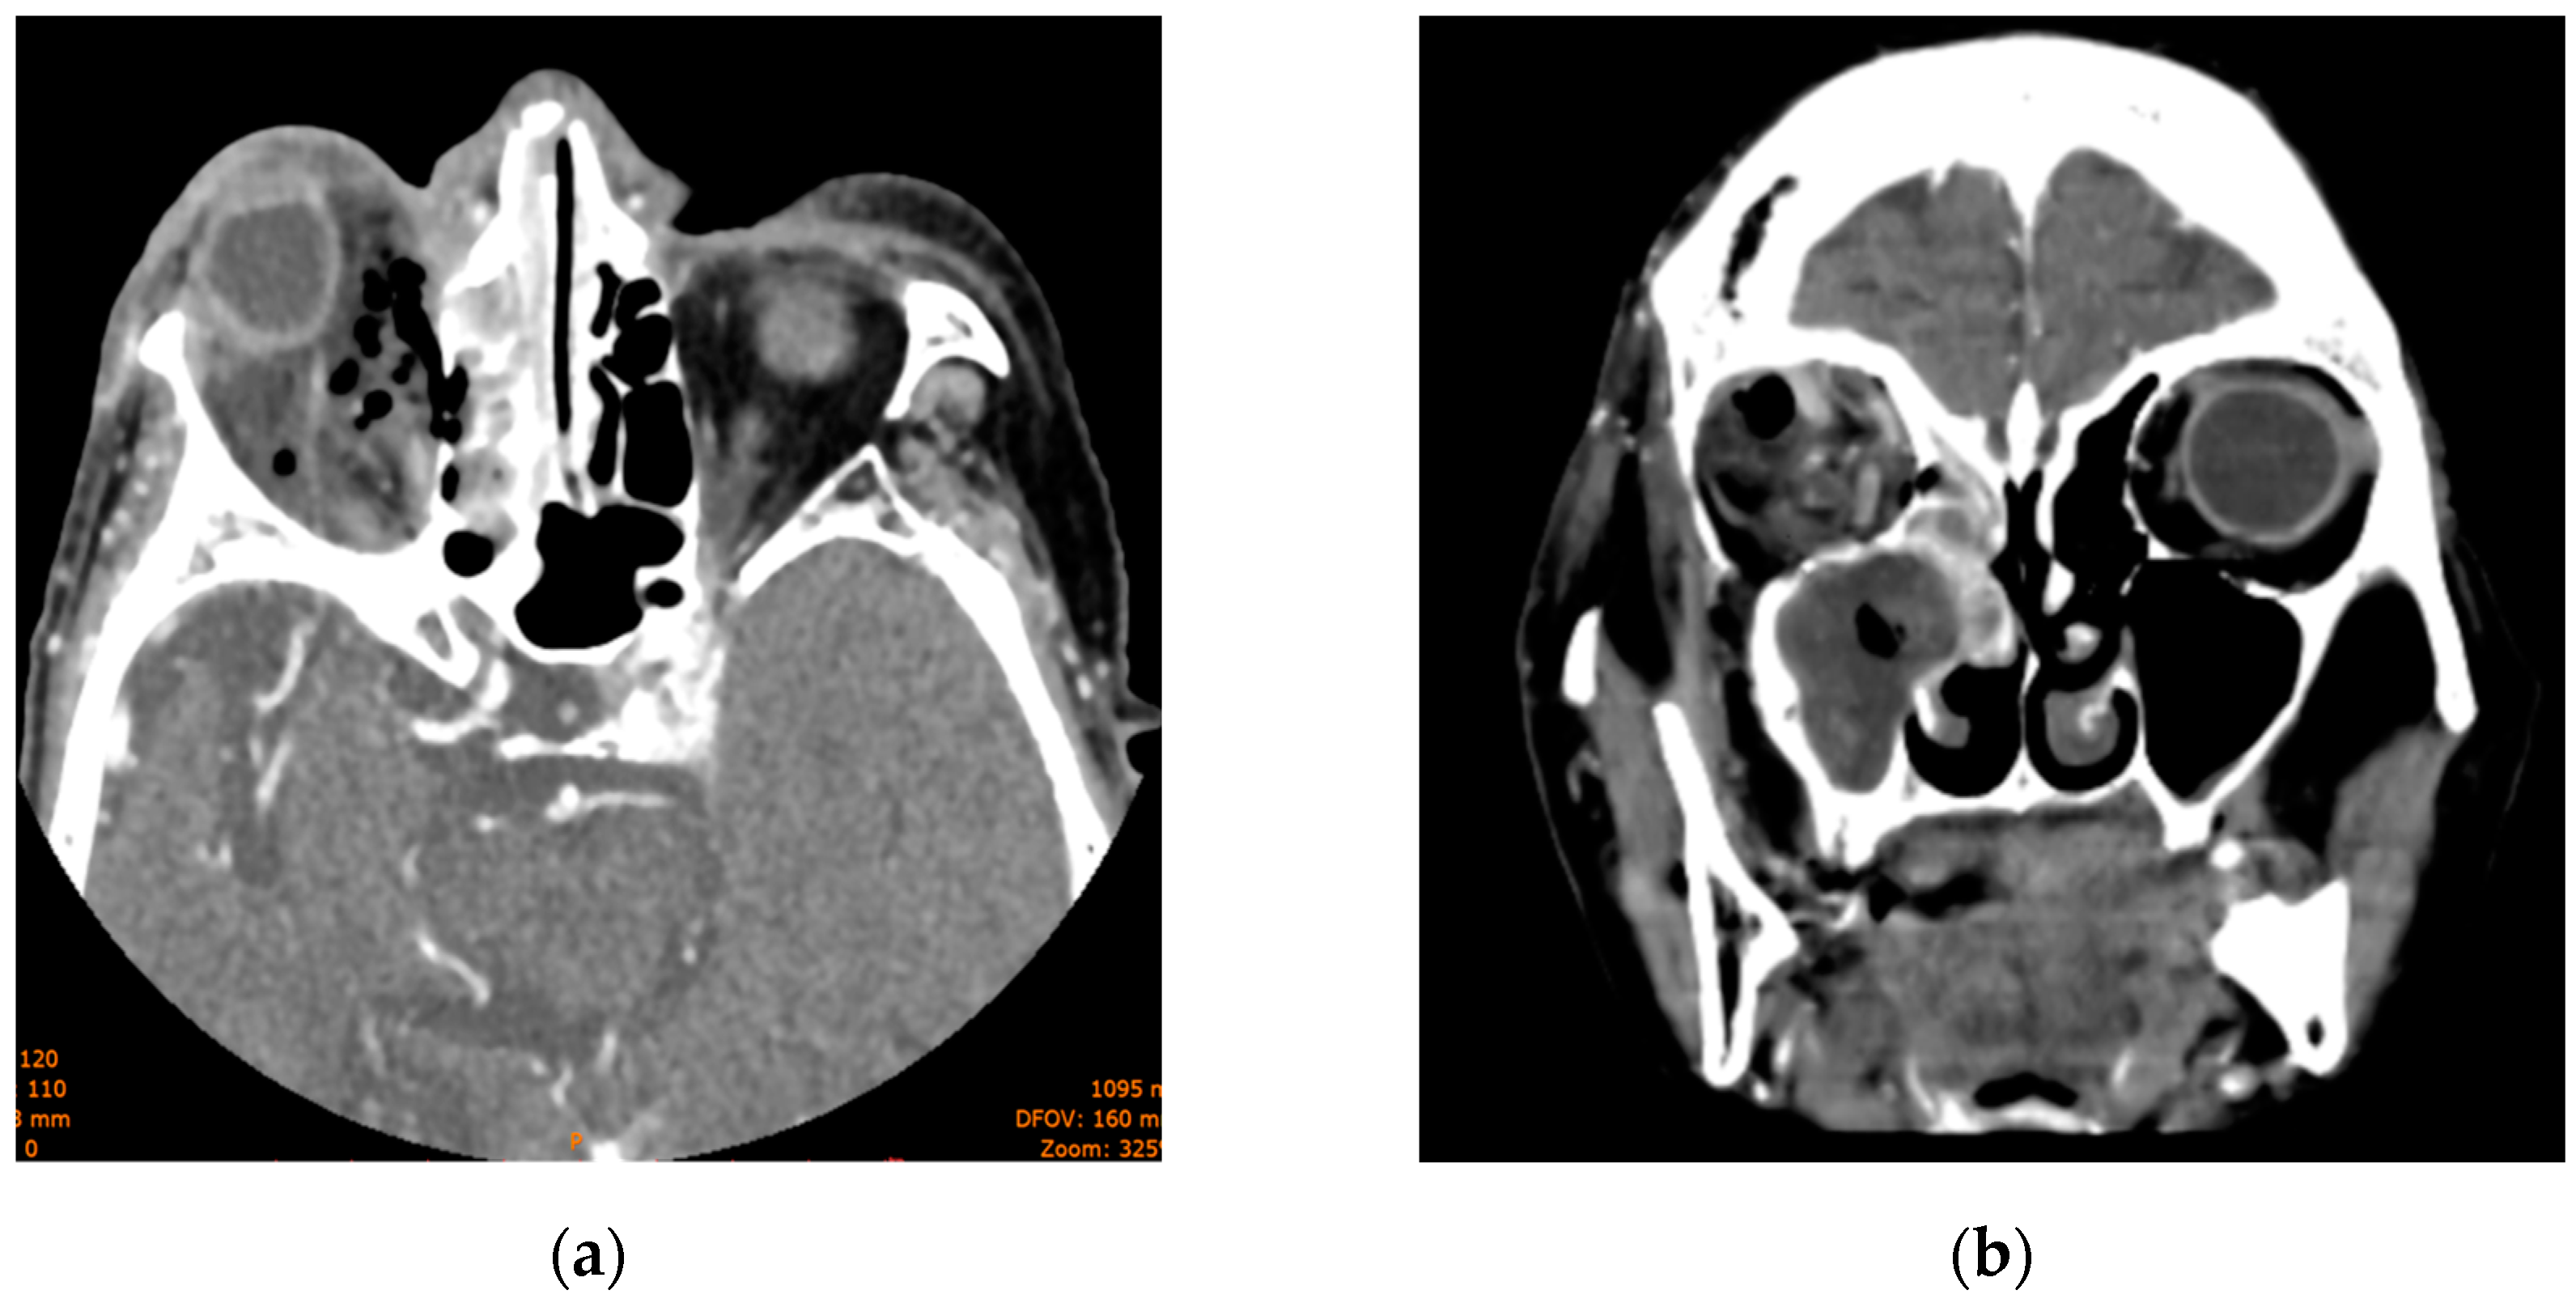

The head CT revealed a large left-sided orbital abscess of 25 × 14 mm, a left preseptal eyelid abscess with a thickness of 9 mm, left maxillary sinus opacification, posterior globe tenting, and retromaxillary soft tissue swelling with a thickness of 7 mm with extension in the orbit via the inferior orbital (Figure 10).

Figure 10. Computed tomography scan section displaying (a) coronal section with maxillary sinus opacification and orbital abscess; (b) axial section with maxillary sinus opacification.